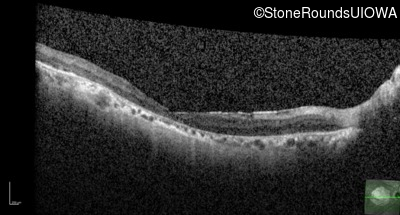

AR Stargardt Disease (IIA)

Age at visit:

79 years

OD

OS

20/250 sc

AR Stargardt Disease

ABCA4

Gly607Arg GGG>AGG

IVS30+1321 A>G

AR